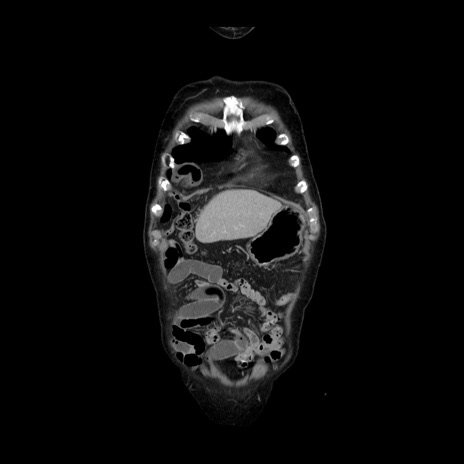

横断像